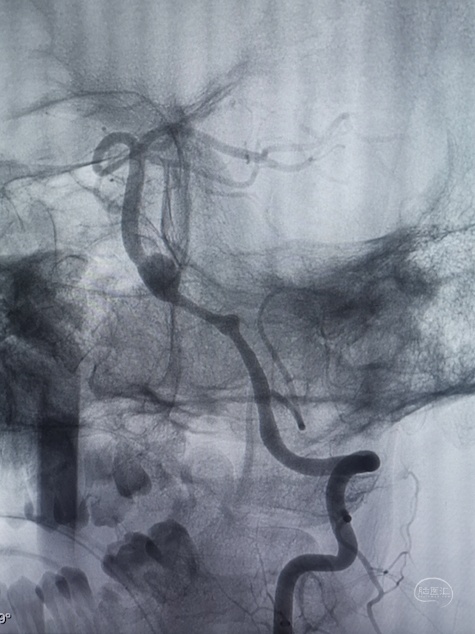

DSA:

3D重建显示基底动脉下部、双椎结合部、左椎多发夹层动脉瘤: